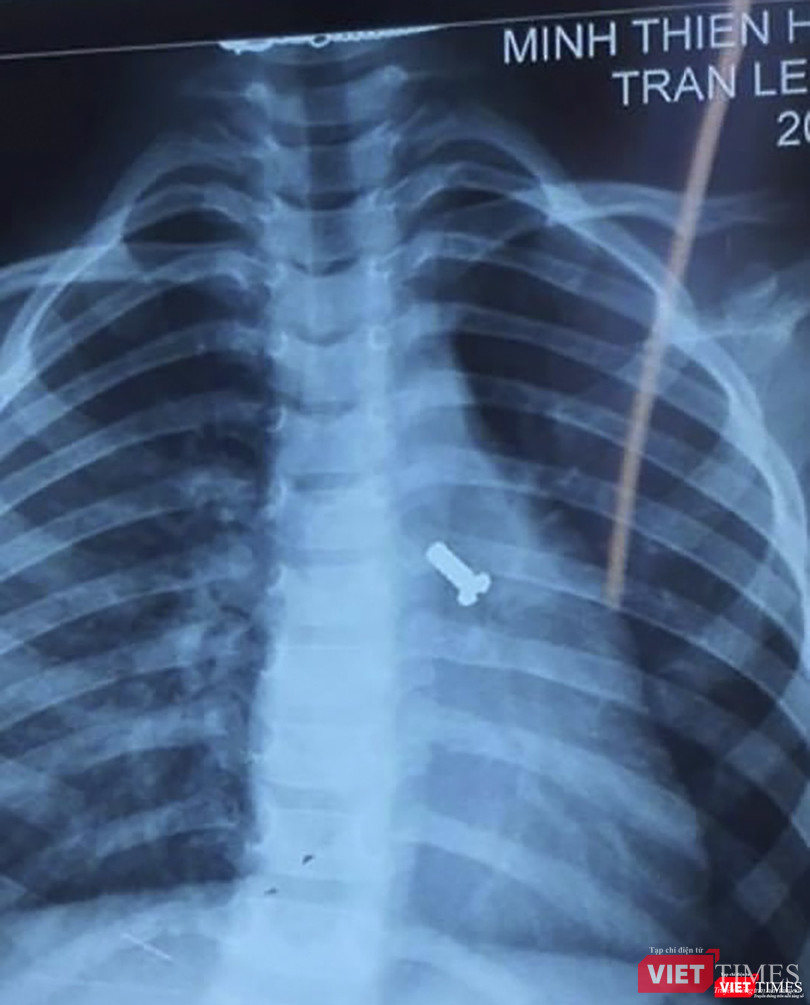

“Bệnh nhân N. nhập viện trong tình trạng khó thở đột ngột, cơ thể tím tái không rõ nguyên nhân nên gia đình đã đưa vào bệnh viện cấp cứu. Qua thăm khám và chụp X-quang, chúng tôi đã phát hiện một ốc vít nằm ở đường thở của trẻ” - bác sĩ CKII. Lê Mạnh Hoàng-Trưởng khoa Mắt-Tai Mũi Họng-Răng Hàm Mặt (Bệnh viện Phụ sản - Nhi Đà Nẵng) - cho biết.

| Phim X-quang đinh vít nằm ở đường thở của trẻ |